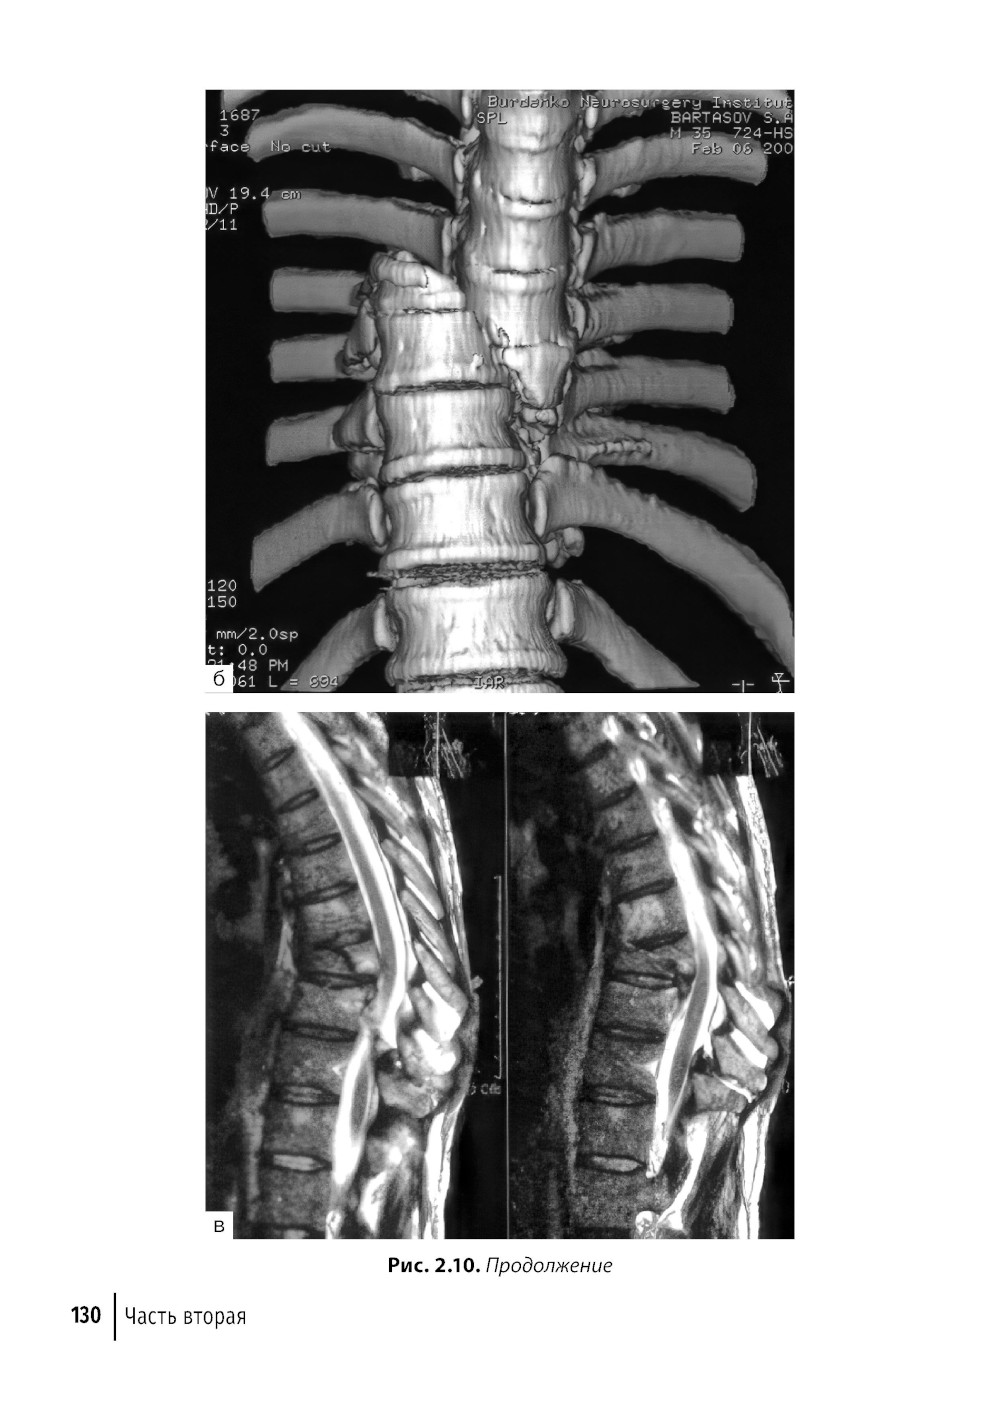

Хирургическое лечение заболеваний и повреждений позвоночника и спинного мозга в последнее время становится очень актуальным. Оно позволяет устранить причину болей и неврологических проблем, связанных с деформацией, нестабильностью позвоночника и сдавлением спинного мозга и его корешков. Появление современных методов диагностики заболеваний, новых малоинвазивных доступов, специального микрохирургического инструментария позволяет сделать хирургию позвоночника высокотехнологичной и безопасной. Быстрое восстановление качества жизни больных после операции и отсутствие необходимости проведения длительного реабилитационного лечения делают хирургию позвоночника основным методом лечения данных заболеваний. Руководство посвящено современным возможностям хирургического лечения этой распространенной патологии. В нем описаны современные, наиболее часто используемые вмешательства на позвоночнике и спинном мозге. Приведены схемы, рисунки и фотографии хирургических доступов и клинических примеров. Все это позволяет лучше разобраться в проблеме, правильно поставить диагноз, выбрать оптимальную тактику хирургического вмешательства и добиться хороших результатов лечения у этой многочисленной и сложной категории больных. Первая часть книги посвящена технике хирургического вмешательства на шейном отделе, вторая часть - на грудном и поясничном отделах позвоночника. Издание предназначено нейрохирургам, травматологам-ортопедам, неврологам и другим специалистам, занимающимся лечением повреждений и заболеваний позвоночника, студентам медицинских вузов.